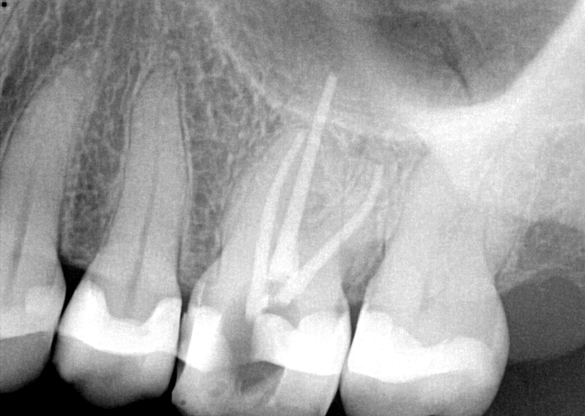

Fig 7. Primary endodontic and secondary periodontal lesion, mandibular second molar.

Figure 7

Treatment of combined endodontic and periodontal lesions does not differ from the treatment of either an endodontic lesion or a periodontal lesion. The part of the lesion sustained by the root-canal infection can usually be expected to resolve after proper endodontic treatment. Timing of the completion of the root-canal therapy, medicaments used, and assessment of restorability are considerations for the long-term success and survival of the tooth.7 Figures 7, 8, and 9 represent the timing of completion and restorative decision-making to complete all therapies.

In Figure 7, the periapical radiograph identifies the presence of the combined endodontic-periodontal lesion developing due to a carious lesion beneath an existing vintage gold crown with ill-fitting margins. Intraoral examination revealed a fistula developing and moderate pain on percussion and mastication. After occlusal access and clear visualization of the canals, the canals were shaped using the rotary files, with precautions taken not to perforate or enlarge the apical foramen. Maintaining the endodontic therapy within the canals prevents the infection from being introduced into the surrounding periodontium. In this case, calcium hydroxide medicament was placed into the canals and evaluated 30 days postoperatively.8